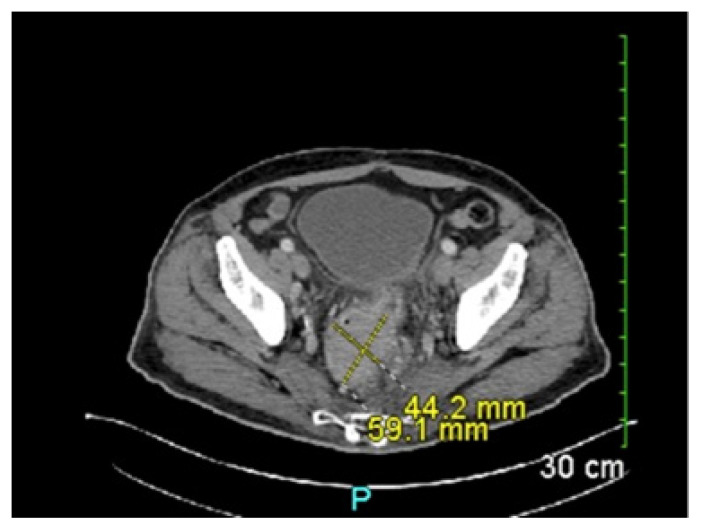

An Alteration to Standardized Treatments: Defunctioning Colostomy in Ultra-Low Stage IIIC Rectal Adenocarcinoma.

Abstract Image